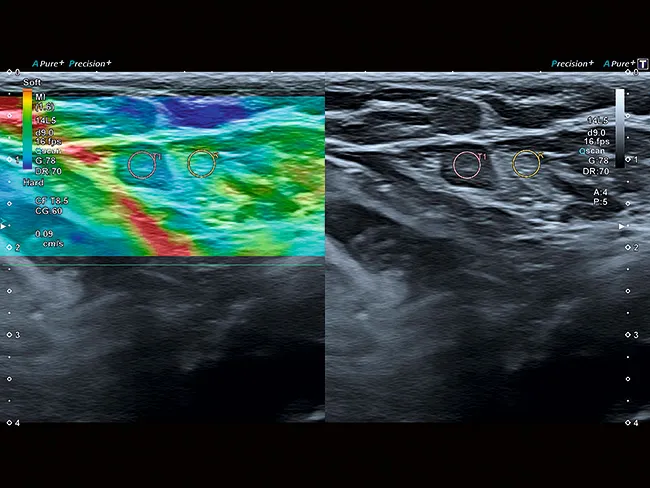

Комплексная система тензоэластографии с функциональными возможностями обработки исходных данных помогает вам локализовать и оценить пальпируемые образования с высокой точностью, чувствительностью и воспроизводимостью.

Технология сдвиговых волн Aplio обеспечивает количественное измерение эластичности тканей и отображение ее в режиме реального времени в различных клинических условиях. Интеллектуальные карты помогают визуально оценить распространение и качество эластограммы.